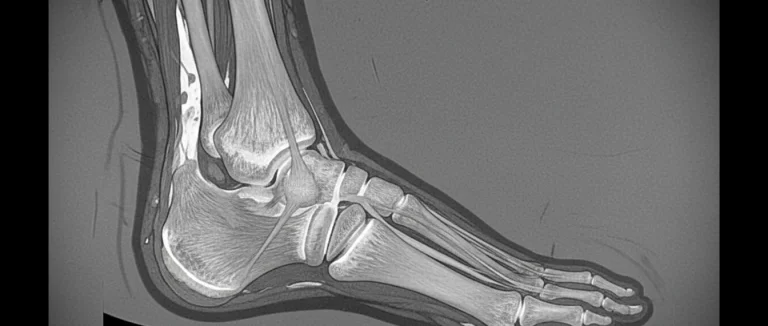

- Магнитно-резонансная томография (MRI): детализирует состояние мягких тканей, сухожилий и хрящей.

В зависимости от результатов, врач может порекомендовать консервативное лечение или обсудить необходимость хирургического вмешательства. При подозрении на сложные повреждения, такие как разрыв ахиллова сухожилия или нестабильность связок, МРТ становится обязательным.

Диагностический процесс начинается со сбора анамнеза и физического осмотра, после чего врач назначает визуализационные исследования. Рентген позволяет быстро выявить переломы и смещения костей. МРТ дает детальное изображение мягких тканей, сухожилий и хрящей, что особенно важно при подозрении на разрывы связок или сухожилий. УЗИ удобно использовать для оценки воспалительных процессов в сухожилиях и синовиальной оболочке. Современное оборудование Лив Хоспитал обеспечивает высокое качество изображений, что помогает точно планировать дальнейшее лечение.